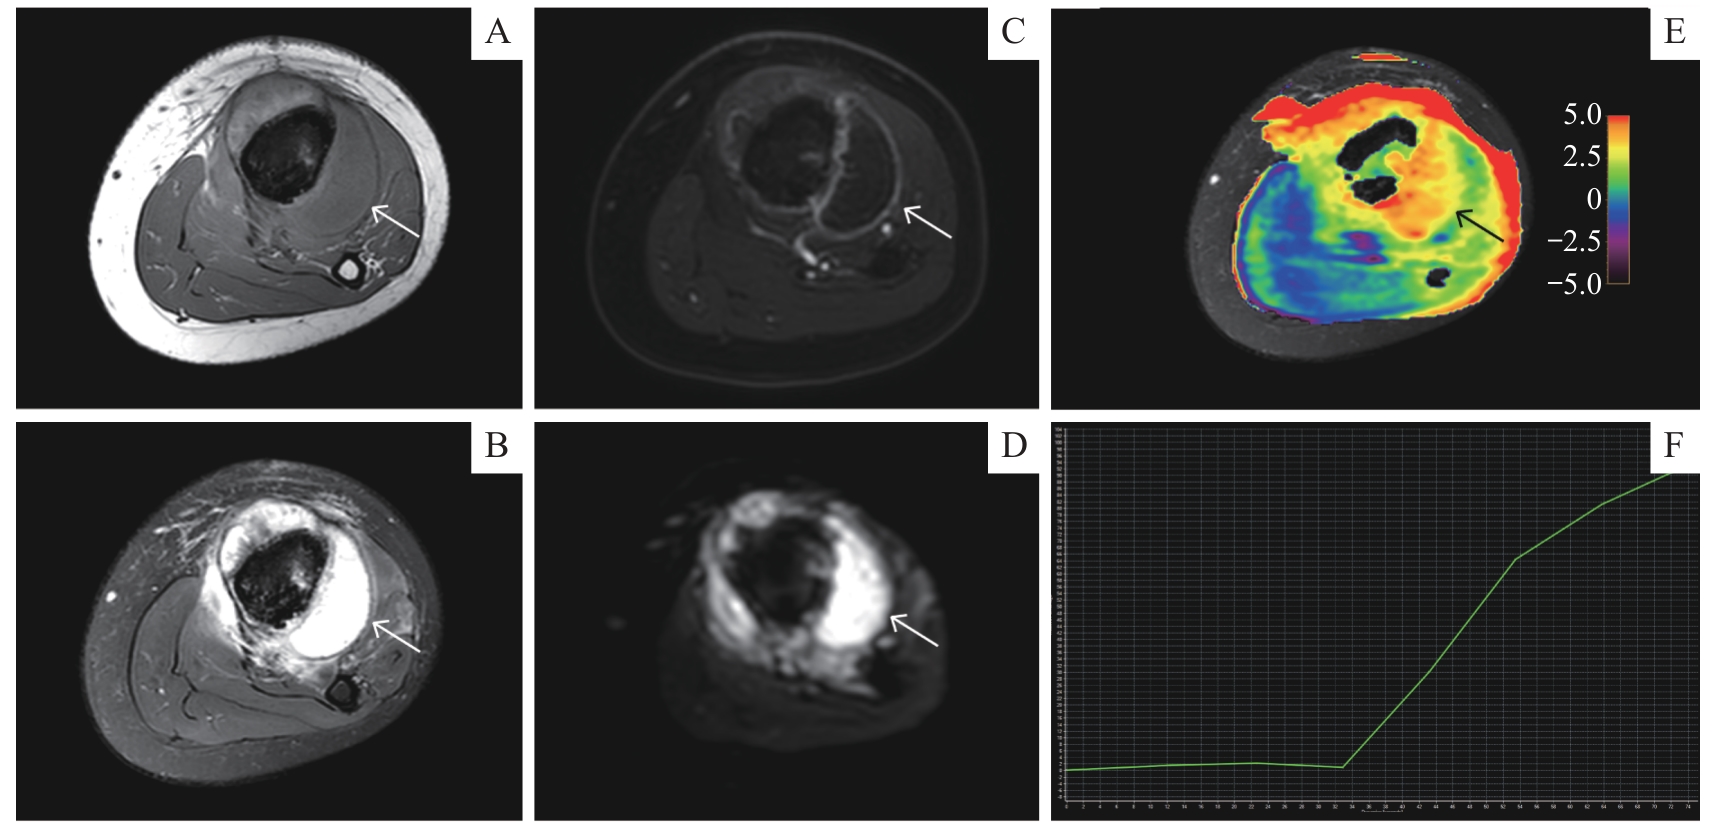

| 图5 APTw成像在恶性骨肿瘤新辅助化疗中的应用 Note: A 12-year-old male with osteosarcoma in the left tibia showed chemotherapy-related changes. A. Axial T1-weighted MRI sequence. B. Axial T2-weighted fat-saturated MRI sequence. C. Axial contrast-enhanced T1-weighted MRI sequence. D. Axial DWI ( b=1 000 s·mm -2) sequence. E. Axial APT image fused with axial T2WI (the color bar indicates the APT values). F. TIC classification (type Ⅰ). |

| Fig 5 Application of APTw imaging in neoadjuvant chemotherapy for malignant bone tumor |